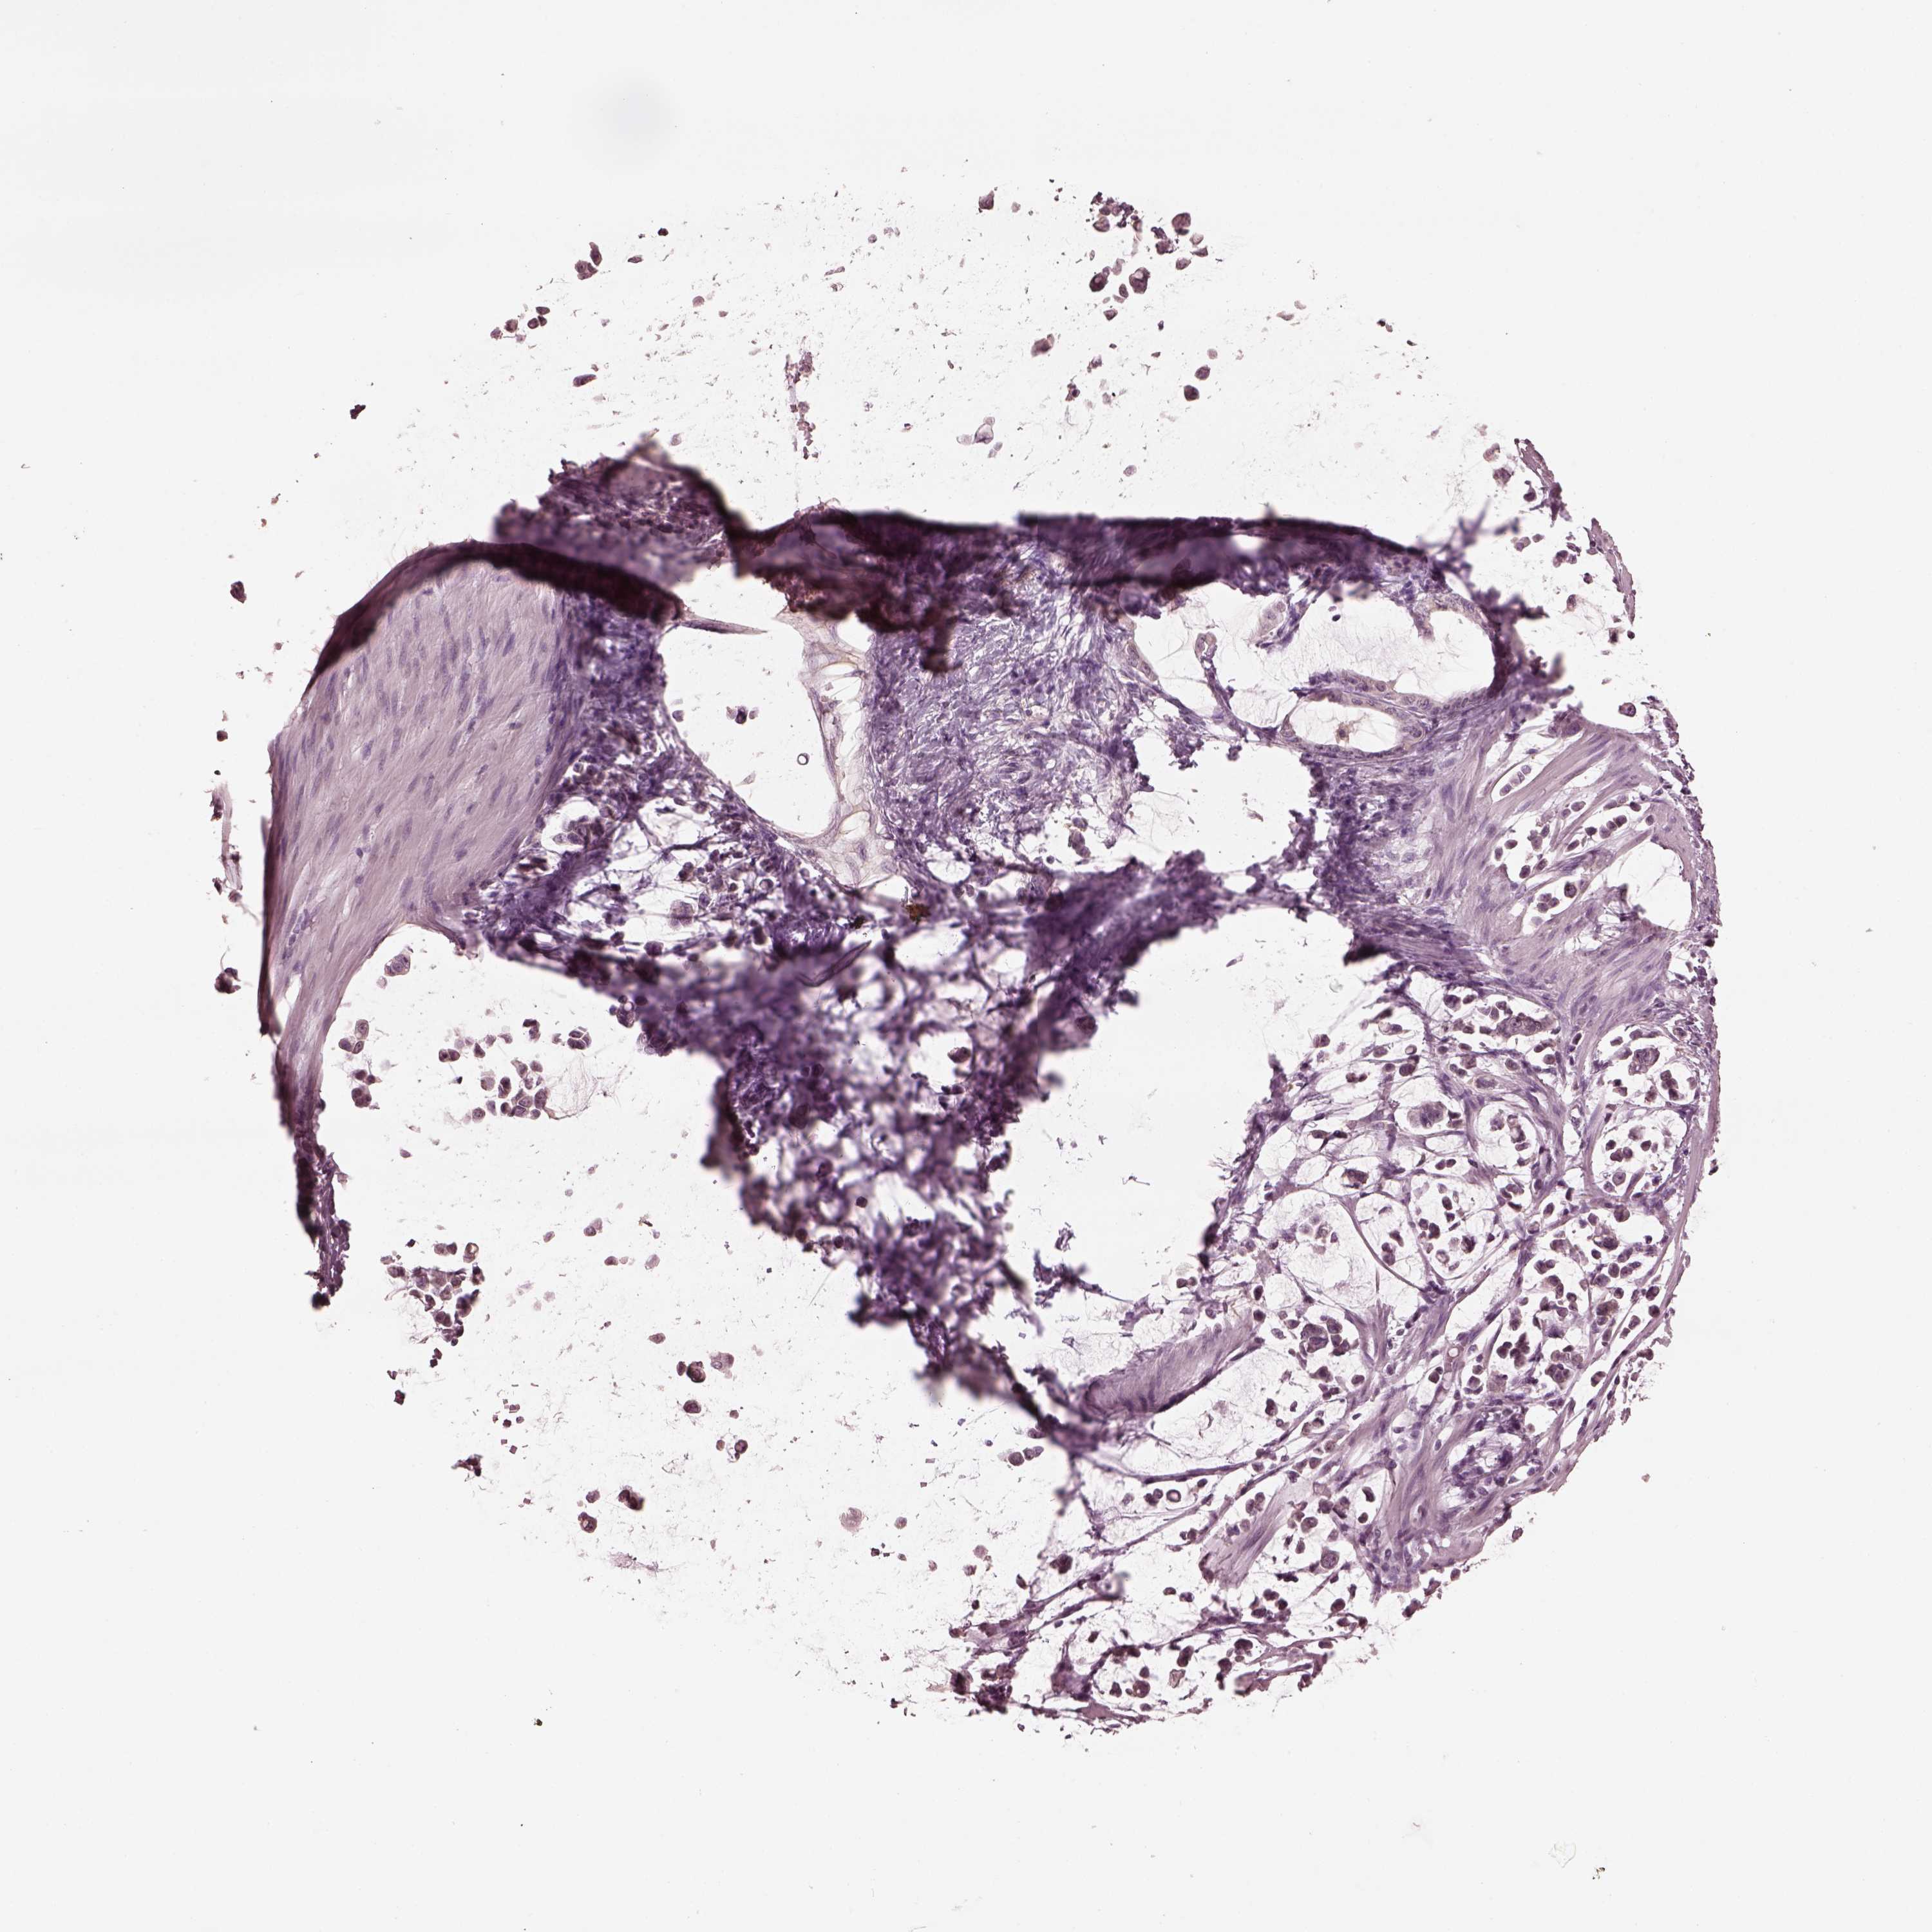

STOMACH CANCER - Protein expressioni

A mouse-over function shows sample information and annotation data. Click on an image to view it in a full screen mode. Samples can be filtered based on level of antibody staining by selecting one or several of the following categories: high, medium, low and not detected. The assay and annotation is described here.

Antibody stainingi

Antibody staining in the annotated cell types in the current human tissue is reported as not detected, low, medium, or high, based on conventional immunohistochemistry profiling in selected tissues. This score is based on the combination of the staining intensity and fraction of stained cells.

Each image is clickable and will lead to virtual microscopy that enables deeper exploration of all samples and also displays staining intensity scores, fraction scores and subcellular localization as well as patient and tissue information for each sample.

Antibody HPA059347

Staining

High

Medium

Low

Not detected

Intensity

Strong

Moderate

Weak

Negative

Quantity

>75%

75%-25%

<25%

None

Location

Nuclear

Cytoplasmic/membranous

Cytoplasmic/membranous,nuclear

Adenocarcinoma, NOS